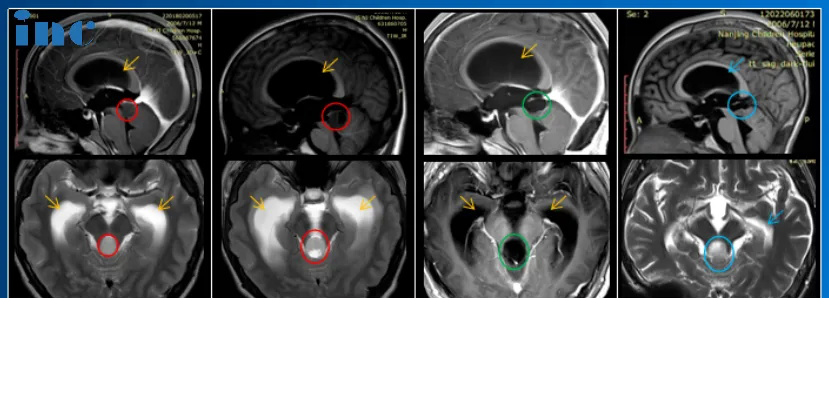

4、14岁男孩——脑干-中脑顶盖毛细胞星形细胞瘤

病情回顾:脑干肿瘤,并伴有梗阻性脑积水,脑室及大脑实质已经受压变形。咨询了很多专家。“每次都说毛细胞星形细胞瘤一般不长,观察就行,但是我然后一次去找他们,我说症状太重,做手术,他们和我说实话,因为做手术风险过大,所以说建议你观察……”这一拖就是2年多,孩子的病情越来越严重。

治疗难点:脑干肿瘤增大,脑积水明显加重,双侧脑室进一步扩大,脑实质压扁。且肿瘤基底部和脑干关系密切、紧邻小脑。

手术结果:术中教授在保全患者正常功能神经和脑干等重要脑组织的前提下,完成肿瘤近全切手术,术后无新发长期性后遗症。小永还凭借的中考成绩,考入国内高中,其中体育成绩还获得了满分,完全看不出来他以前做过开颅手术。

6、6岁男孩——小脑-脑干毛细胞星形细胞瘤

病情回顾:一场小小的交通事故后总是抱怨头晕,为明确有没有大脑损伤,担心后遗症,辰辰妈妈带他到医院做了核磁共振,结果竟然查出“小脑占位”。

治疗难点:右侧小脑半球见40mm*37mm大型肿瘤,肿瘤已经压迫四脑室和脑干,中线结构也开始左移。脑干是生命的中枢,几乎管辖着生命的。肿瘤压迫脑干,意味着生命中枢受到威胁。然而想要顺利手术铲除肿瘤难度更大,手术稍有不慎就可能出现瘫痪、长期昏迷等严重后果。

手术结果:巴教授顺利全切肿瘤,脑干得到充分减压,对中脑的挤压/移位压力明显减少,小脑组织大部分复位,术后2年半没有复发、无后遗症。